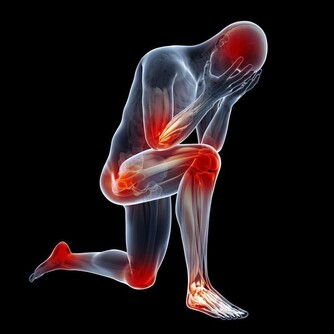

4、骨骼強壯中醫認為,腎主骨,骨靠腎精滋養,腎好骨才好。

腎氣衰敗會出現骨質疏鬆、腰酸背痛,甚至牙齒出現鬆動。